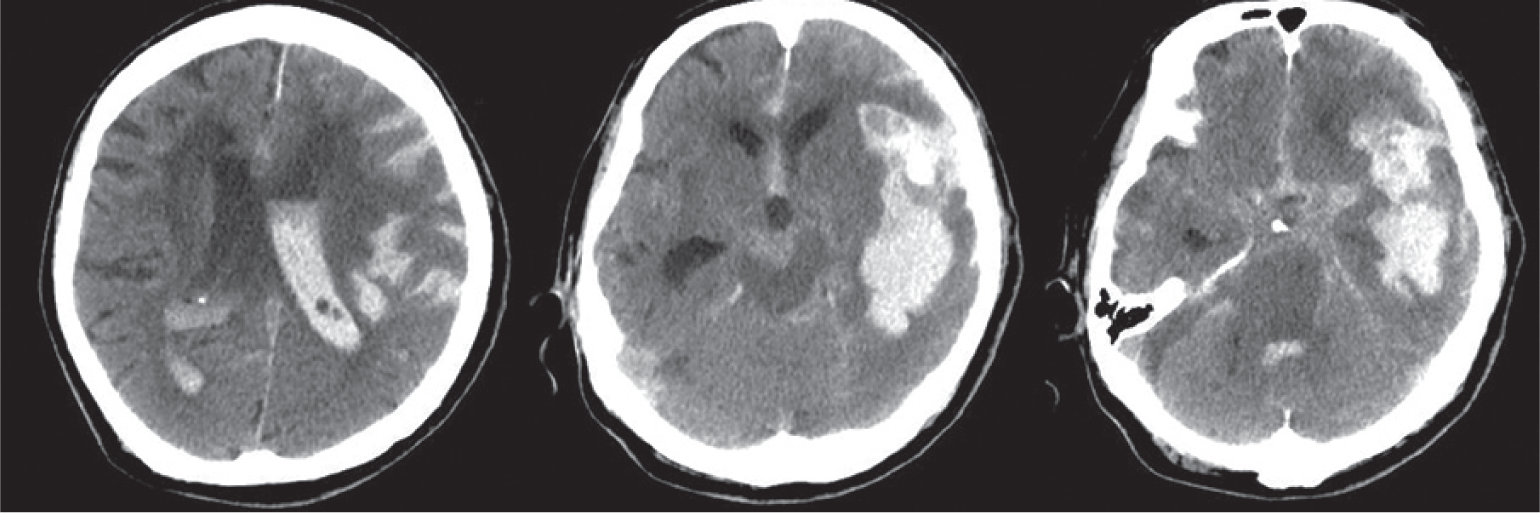

• Current clinical trials are attempting to achieve maximal intracerebral hemorrhage evacuation with nondisruptive surgical access modalities. For instance, the ENRICH trial seeks to compare outcomes between standard medical management to early ( < 24 hours) surgical hematoma evacuation using minimally invasive parafascicular surgery. The estimated study completion date is July 2020.